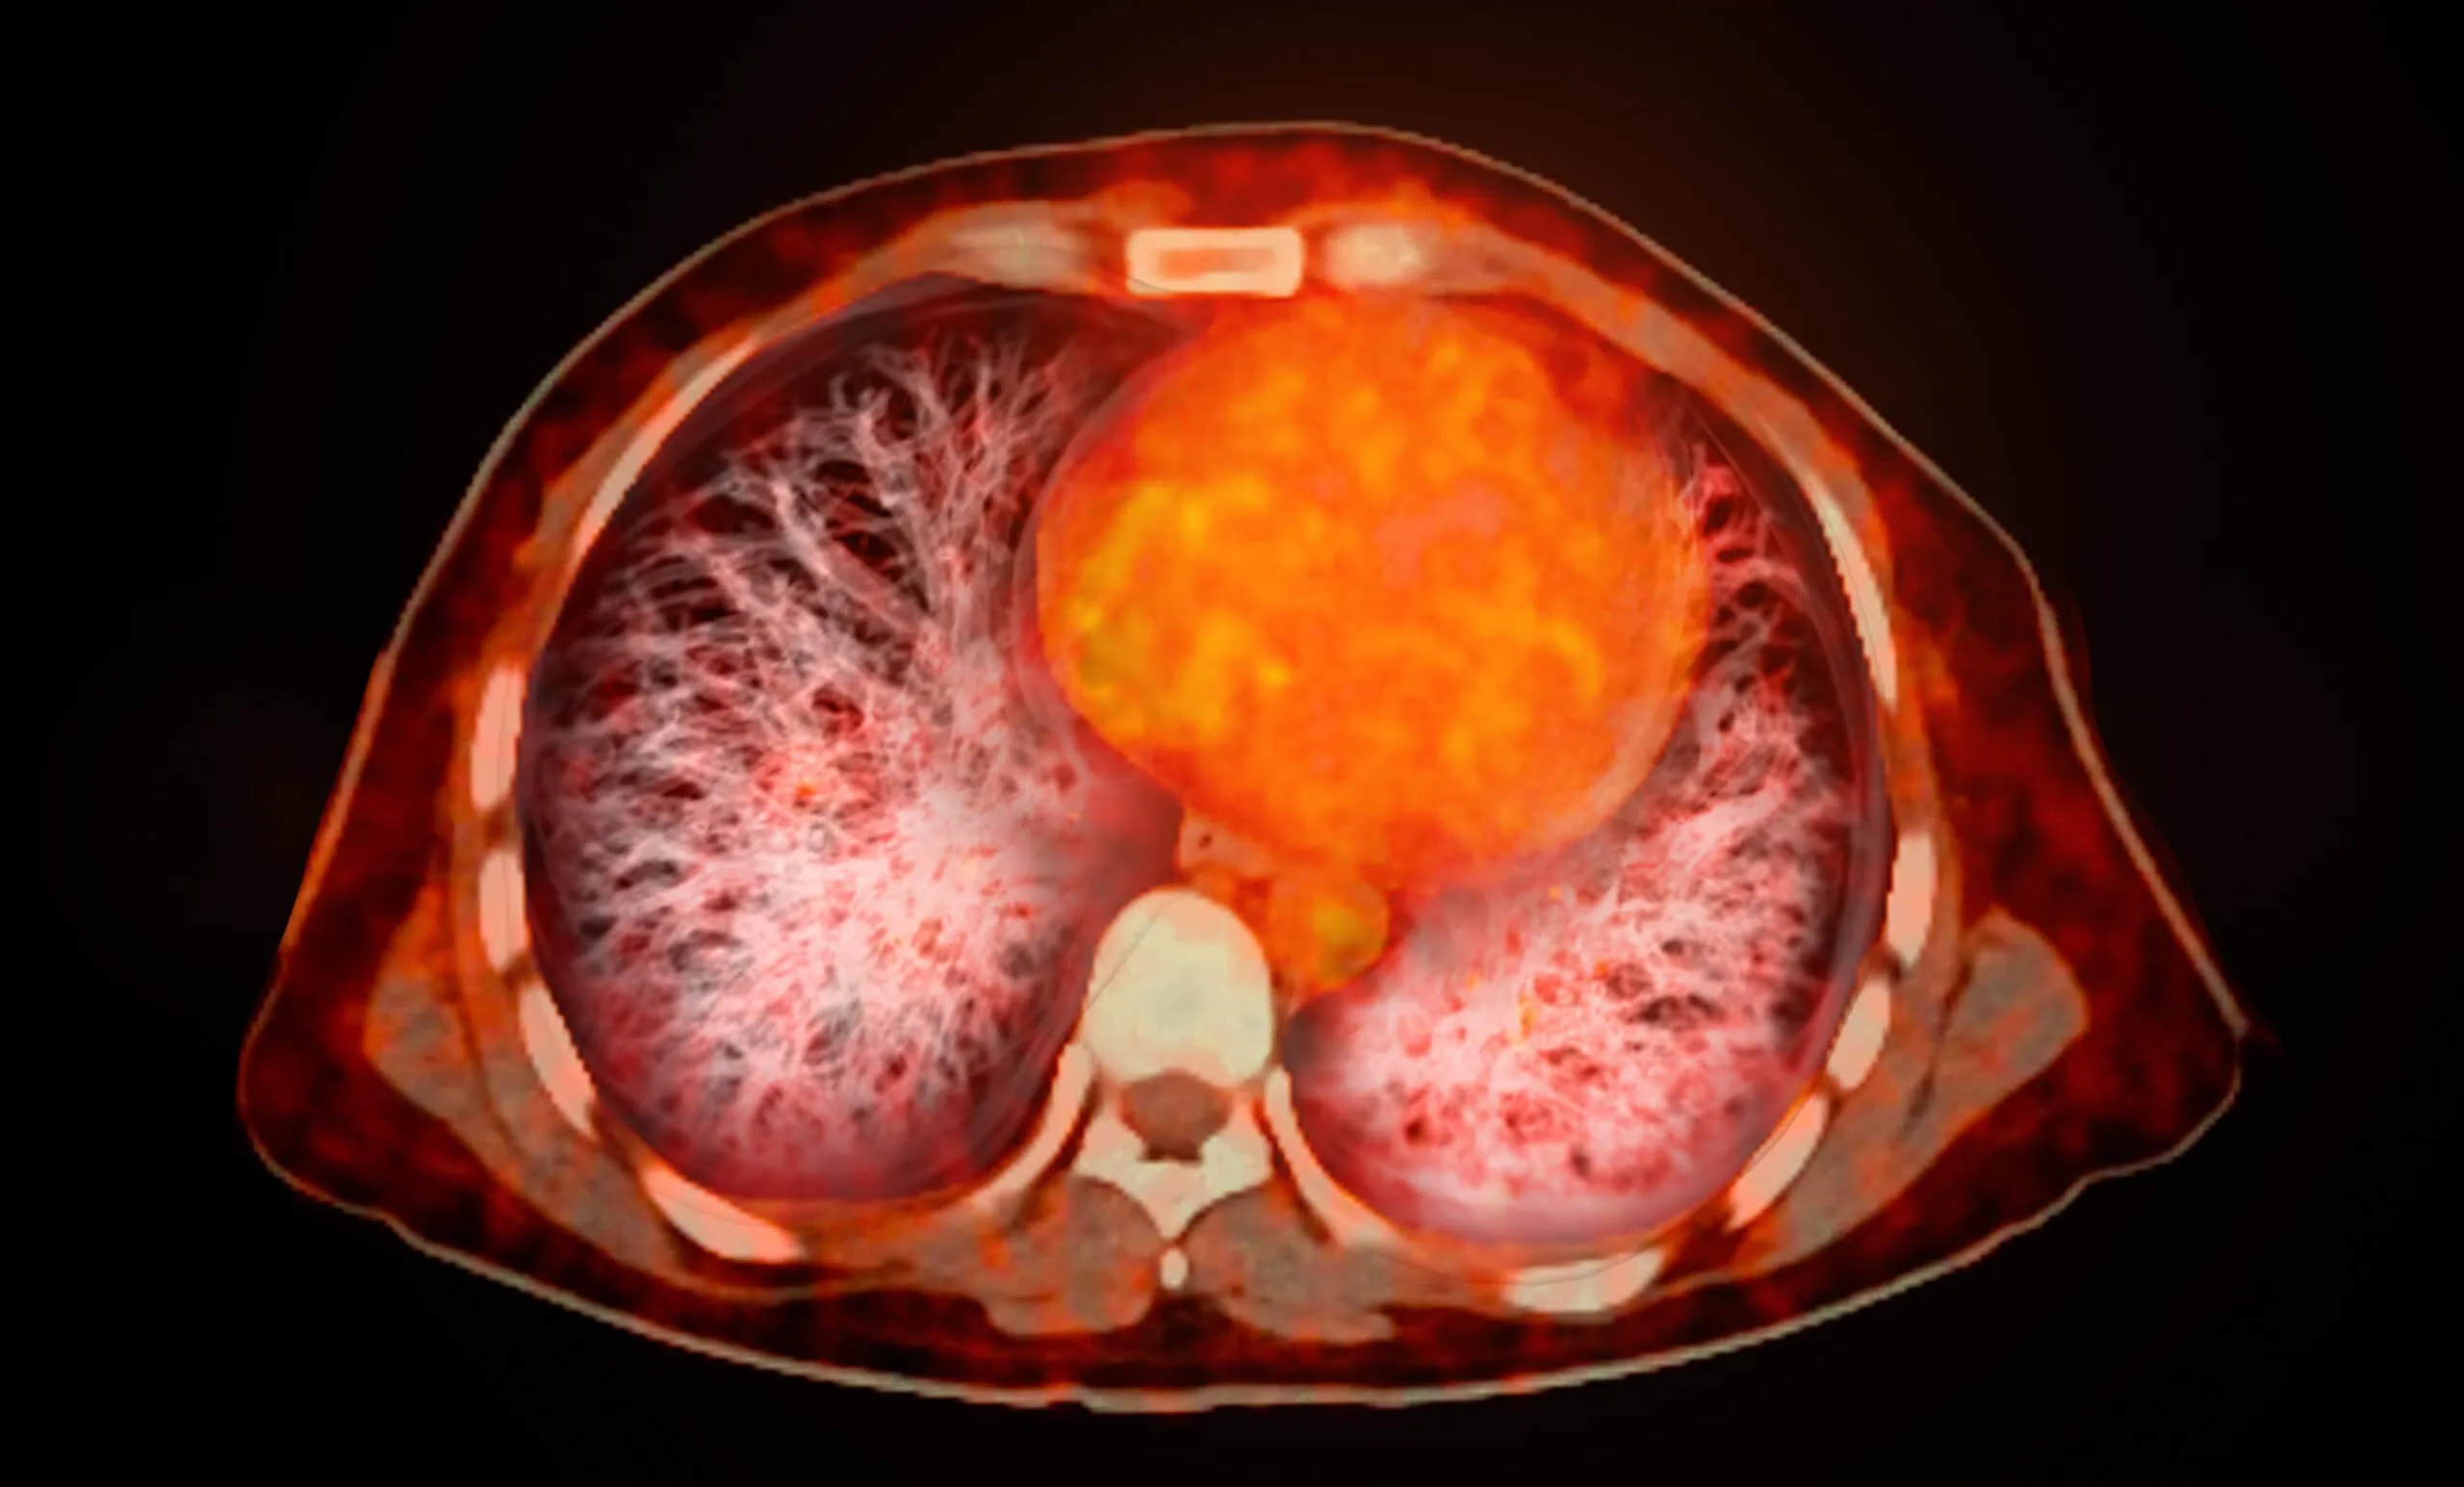

Os exames de PET-CT proporcionam informações resultantes de dados funcionais e morfológicos, a partir da combinação da análise da distribuição do rádiofármaco com a anatomia retratada pela tomografia. A resultante final representa muito mais do que o somatório das duas técnicas, contribuindo substancialmente na tomada de decisão em Oncologia.

Os avanços mais recentes nos estudos de PET-CT têm ocorrido sobretudo no desenvolvimento de novos radiotraçadores, destacando-se o uso de radiofármacos já consagrados na literatura, como FDG (glicose radiomarcada) para diversos tipos de neoplasias, agora somado ao PSMA e FES, no manejo clínico do câncer de próstata e mama, respectivamente. Os radiofármacos empregados nos exames de PET/CT do Serviço de Medicina Nuclear do RICHET – Medicina & Diagnóstico tem as suas aplicações baseadas de forma consistente no estado da arte da tecnologia e do conhecimento médico.